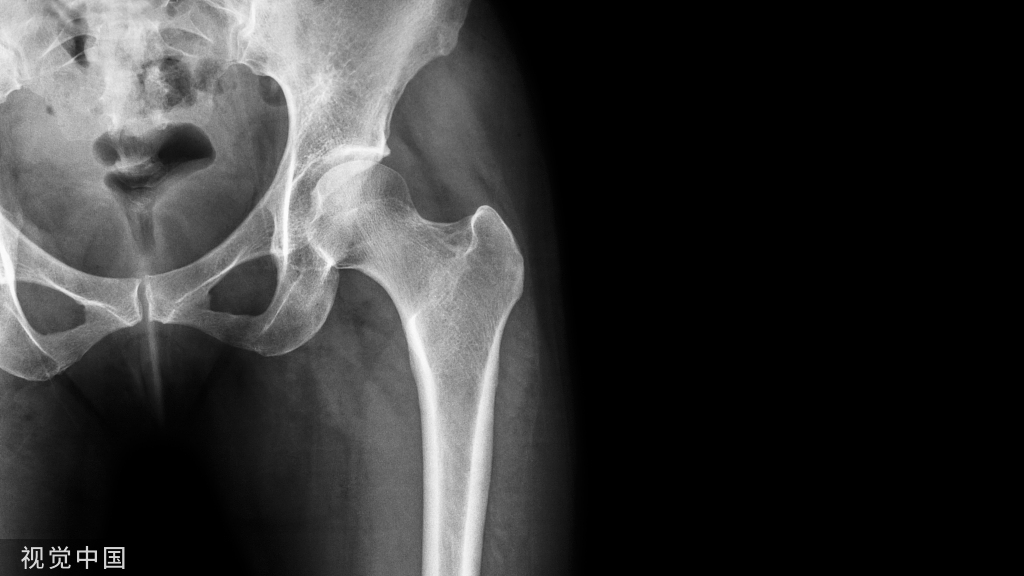

前后移位

对于前后移位就相对复杂一些1、解锁脊柱的关节面